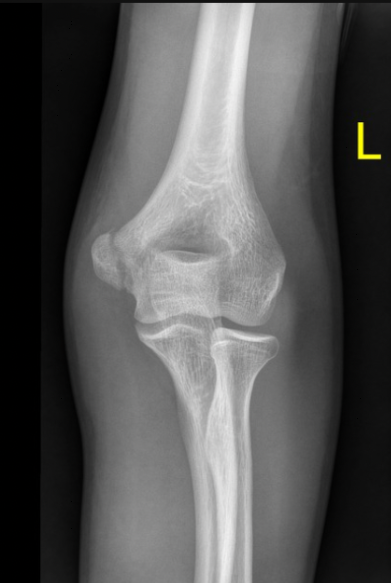

A 21-year-old female presents to the emergency room after falling from dancing on a table and injuring her right ankle. She is in severe pain and unable to bear weight comfortably with swelling and tenderness along the lateral malleolus. X-rays are taken and shown above.